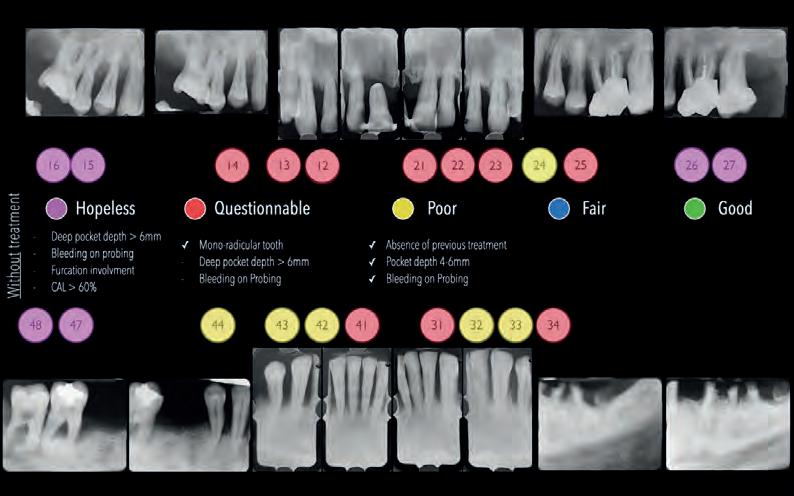

MANAGEMENT OF PERI-IMPLANTITIS IN THE AESTHETIC ZONE

The management of peri-implantitis cases in aesthetically demanding areas is a highly relevant clinical challenge due to the increased risk of mucosal recessions subsequent to the treatment. The exposure of the implant surface may result in an aesthetically unacceptable outcome. Thus, the additional goal of peri-implantitis management in aesthetic areas is the preservation of the esthetics.

The lecture will elaborate on the remodeling process that peri-implant tissue undergoes following the surgical peri-implantitis treatment. It will further address the step-by-step surgical treatment protocol for the management of peri-implantitis cases in the aesthetic zone and the rationale for soft-tissue grafting as part of the treatment protocol. Clinical scenarios resulting in unacceptable aesthetic outcomes requiring implant removal and the “second-round” implant planning will be further discussed.